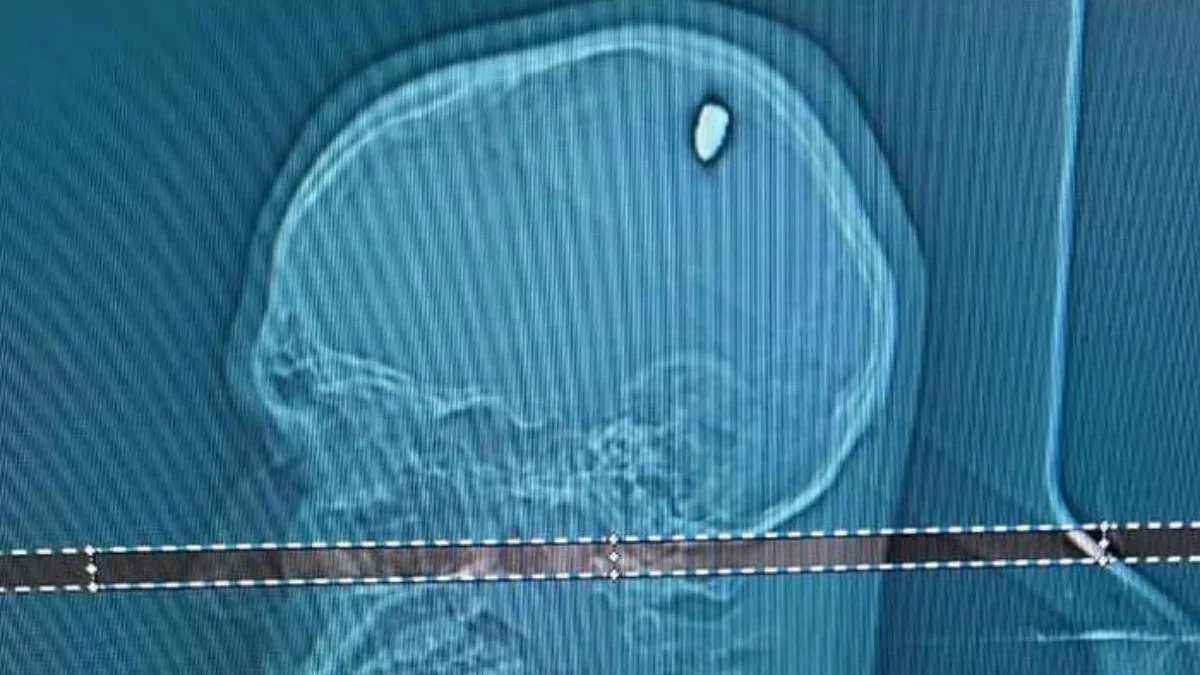

Lantaran khawatir dengan kondisinya, Mateus langsung pergi ke rumah sakit setempat untuk memeriksakan diri. Berdasarkan hasil pemeriksaan CT scan, dokter menemukan bahwa ada peluru 9mm yang bersarang di kepalanya, yang awalnya dikira hanyalah lemparan batu saja.

Dokter kemudian langsung merencanakan operasi pengangkatan peluru dari otak Mateus. Meskipun ada risiko yang terkait dengan prosedur tersebut, tetapi operasi itu telah berhasil dilakukan, dan Mateus kini sedang dalam tahap pemulihan. (*)